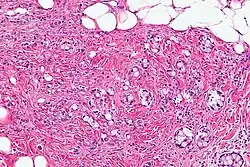

| Micrograph showing a goblet cell carcinoid. H&E stain. | |

The goblet cell carcinoid (GCC) is a rare biphasic gastrointestinal tract tumour that consists of a neuroendocrine component and a conventional carcinoma, histologically arising from Paneth cells.[1]

GCCs are diagnosed by pathology. They have a characteristic biphasic appearance which includes (1) goblet cell-like cells, and (2) neuroendocrine-type nuclear chromatin (stippled chromatin).